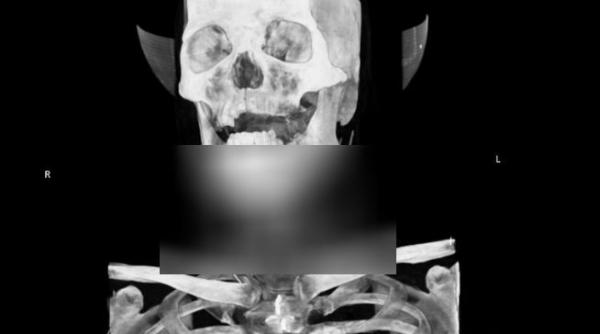

CAZ UNIC ÎN LUME! Medicii italieni, ŞOCAŢI de ceea ce au văzut în radiografiile unui pacient. "N-am mai întânit aşa ceva!"